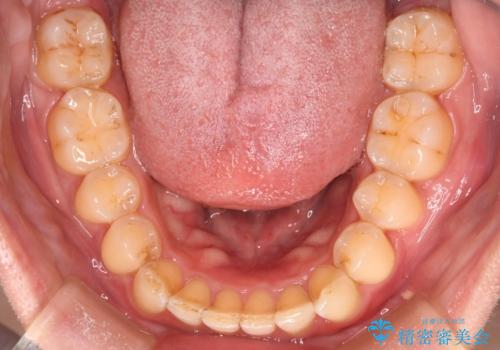

- 下の歯のがたつきを主訴に来院されました。

下の歯のがたつきと右の奥歯の噛みあわせ改善するために治療計画を立てることにしました。

ゴム掛けを頑張っていただいたので、噛みあわせも改善され綺麗な歯並びになりました。